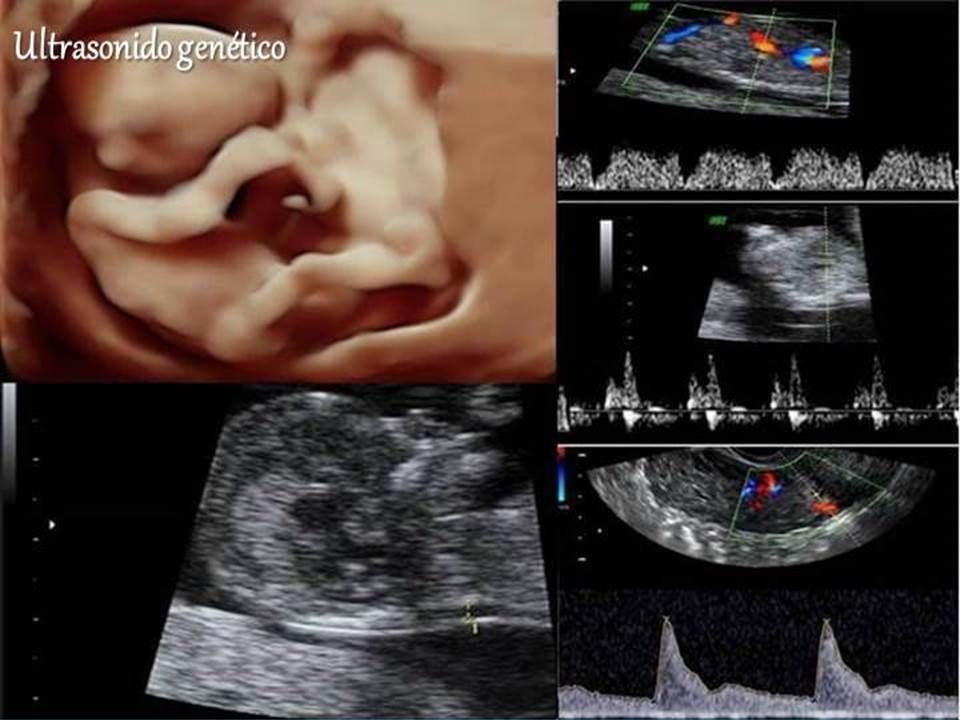

Ofrecemos los estudios de imagen necesarios para descartar malformaciones y para predecir el riesgo de enfermedades cromosomicas (como Sindrome de Down) y de complicaciones en el embarazo.

Contamos con el equipo que actualmente ofrece la mejor resolución disponible, tanto para hacer un diagnostico certero, como para que las futuros papás puedan ver una imagen mas realista de su bebe.

• Medicina materno fetal

• Ultrasonido